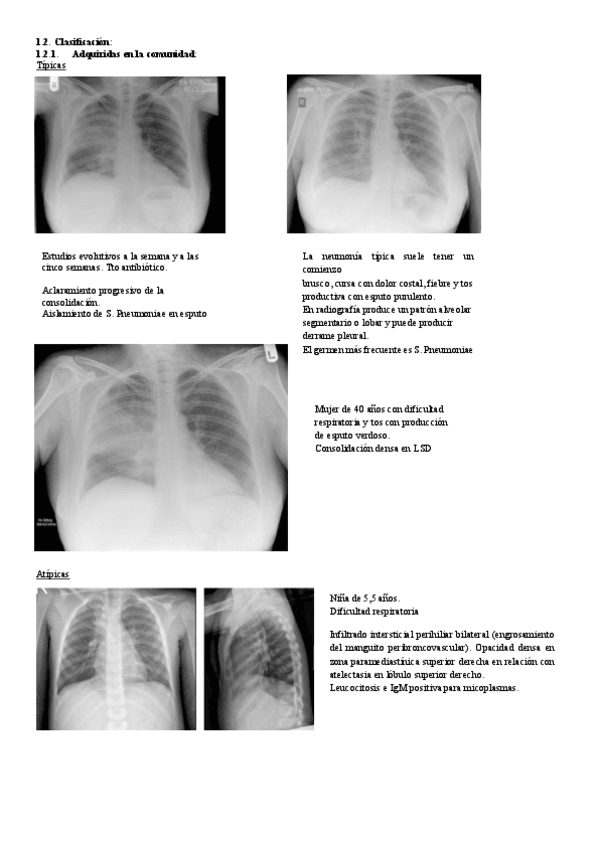

He publicado nuevos apuntes de 3º Radiología y Medicina Física. Protección Radiológica: seminario-ire-infecciones.pdf

60 páginas